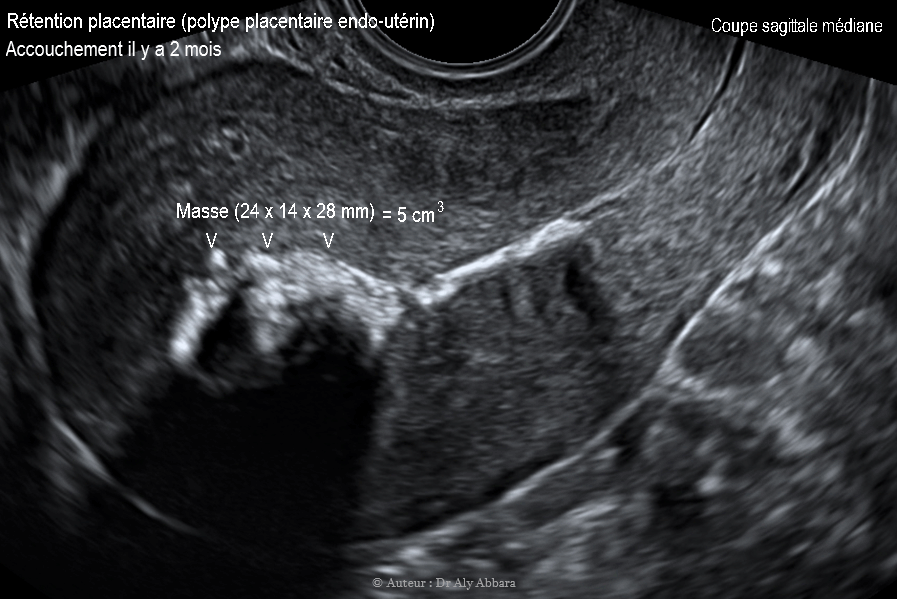

Polype placentaire ou rétention patielle d'un segment du placenta chez patiente ayant accouché par voie naturelle il y a deux mois

• Images échographiques par voie endovaginale montrant la présence d'un polype placentaire (rétention fragmentaire d'un segment du placenta) chez une patiente ayant accouché par voie naturelle il y a deux mois.

• Ce polype placentaire prend l'aspect d'une masse hyperéchogène occupant le fond de la cavité utérine ; de 5 cm3 de volume (24 x 14 x 28 mm de diamètre) ; prenant une forme ovoïde sur la coupe sagittale médiane, et une forme triangulaire et irrégulière sur la coupe transverse de l'utérus.

• Il s'agit d'une découverte fortuite échographique lors de la consultation post-natale.

• Cliniquement la patiente décrit la survenue des règles à deux reprises à intervalle de 15 jours malgré la prise d'un contraceptif estroprogestatif (type 21 jours / 28 jours).